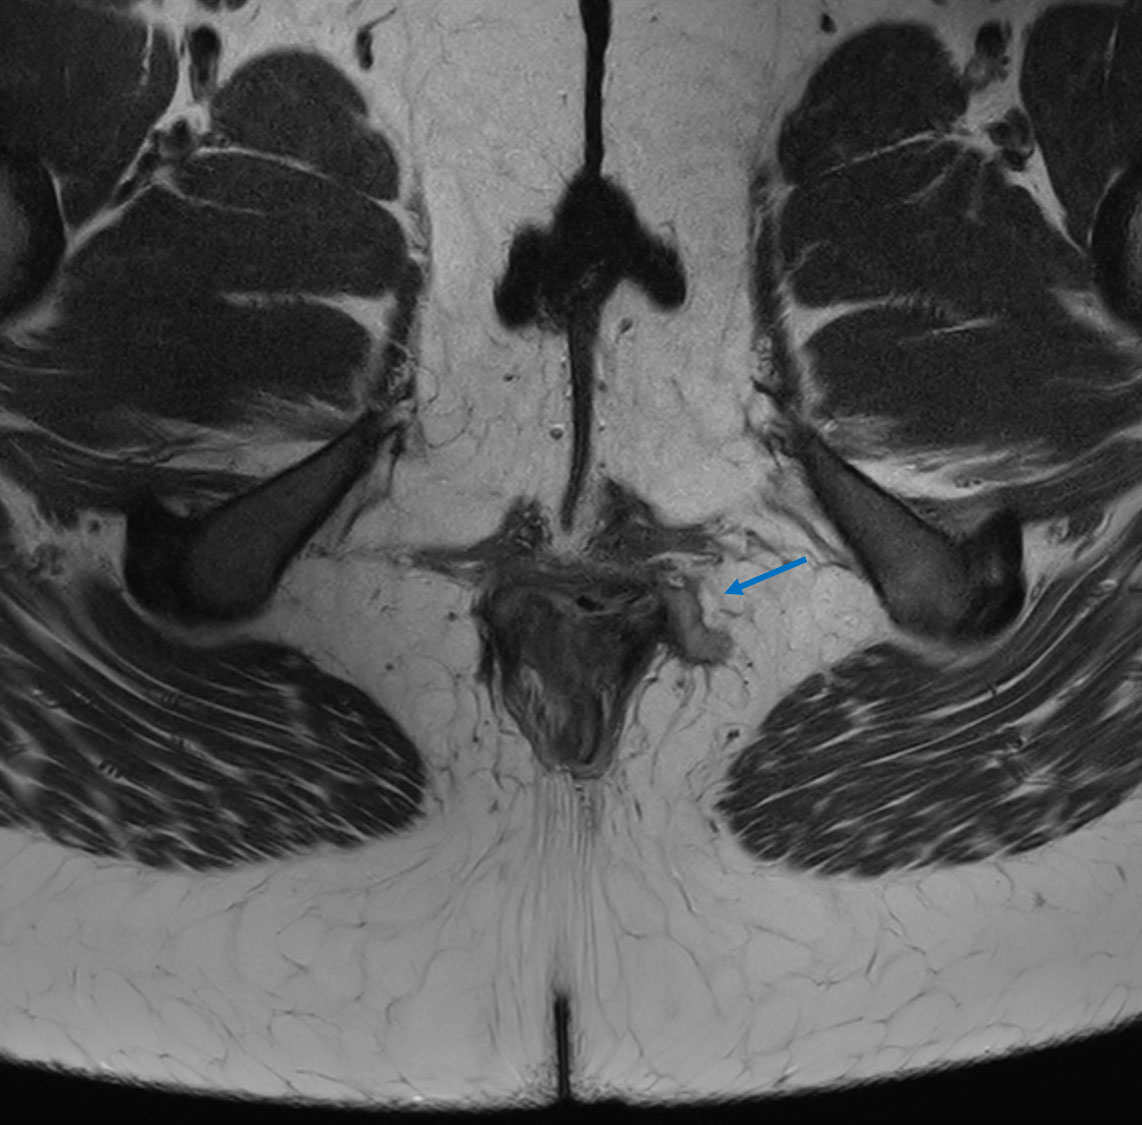

Axial T2w TSE